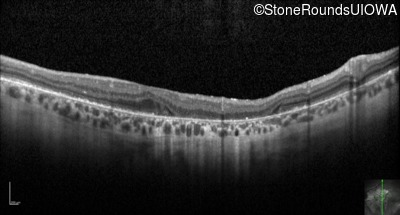

Optical Coherence Tomography - Right - 20/25 -2

Exemplar / OCT Stack